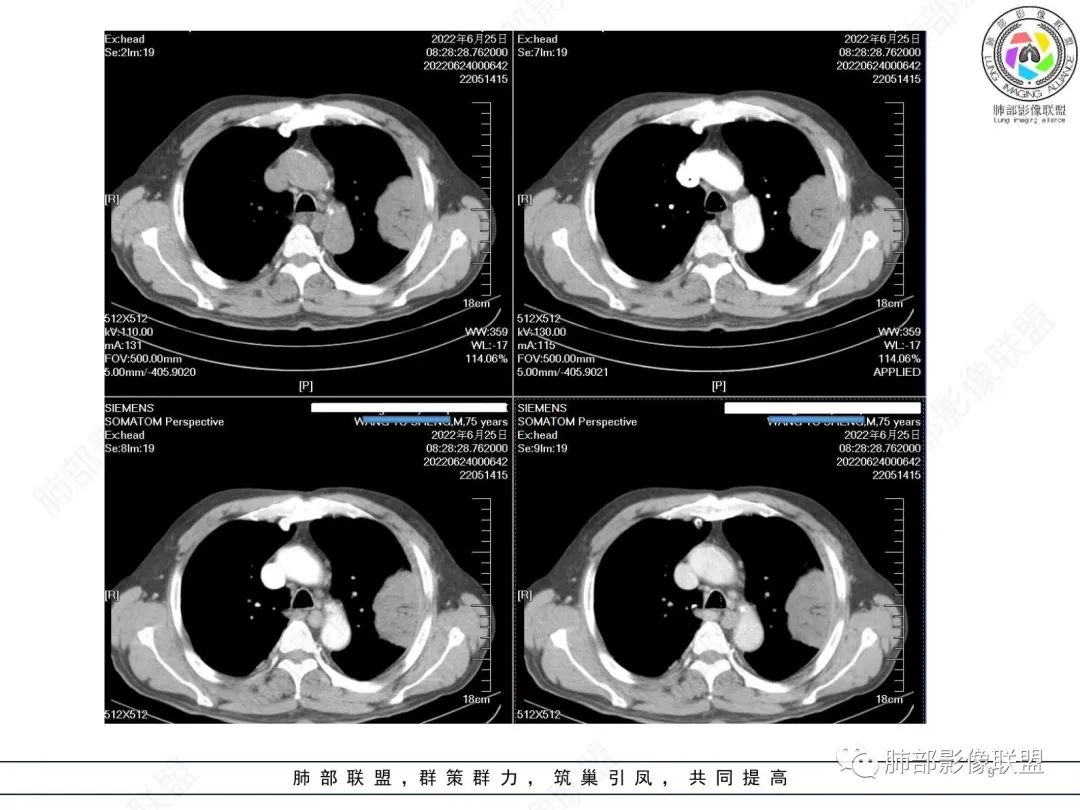

原发性肺肉瘤样癌(PSC)一组临床罕见的肺部肿瘤,属于上皮细胞源性肿瘤,仅占肺部恶性肿瘤的0.3%~4.7%。为含有肉瘤形态细胞或肉瘤样分化的非小细胞肺癌,癌成分多为鳞癌或腺癌,肉瘤成分最常见的是纤维肉瘤。

肺肉瘤样癌的CT表现主要特点:

1)部位:周围型或中央型软组织肿块,以周围型为多见,且肿瘤多位于肺上叶。如本例:该肿瘤位于左肺上叶。

2)大小及形态:由于本病恶性程度高,早期症状不明显,发现时肿块均较大。如本例病变巨大。

3)肿块边界和边缘:多较清楚,呈圆形、类圆形,且由于肿块生长速度不均匀,可见分叶,毛刺少见。有报道肿块周围毛玻璃影是多形性癌特征表现。

4)密度:肿块平扫为软组织密度,由于体积较大,内部常见大片状坏死,可出现不规则厚壁空洞或坏死内多发无壁小空洞,坏死多不均匀:坏死灶内可见如柳絮样的斑片样强化灶,坏死边缘与非坏死区分界不清本例坏死较明显,密度不均匀。

5)肿瘤强化方式:肺部恶性肿瘤强化程度与其血供丰富程度相关,血供丰富多强化明显,反之则较差。由于PSC 周边实性部分富血供及内部黏液变性、坏死,增强后肿块多数呈轻-中度边缘环形强化或不均匀小斑片状强化。国外学者对照病理发现肿瘤细胞或胶原组织增强扫描时强化,无强化的低密度区代表了黏液样变性区和出血坏死区。